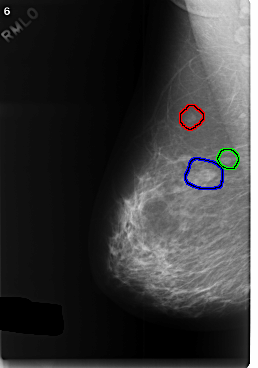

FILE: C_0374_1.RIGHT_MLO.OVERLAY

TOTAL_ABNORMALITIES 3

ABNORMALITY 1

LESION_TYPE MASS SHAPE LOBULATED MARGINS CIRCUMSCRIBED

ASSESSMENT 3

SUBTLETY 5

PATHOLOGY BENIGN

TOTAL_OUTLINES 1

BOUNDARY

ABNORMALITY 2

LESION_TYPE MASS SHAPE ROUND MARGINS CIRCUMSCRIBED

ABNORMALITY 3

LESION_TYPE MASS SHAPE LOBULATED MARGINS MICROLOBULATED